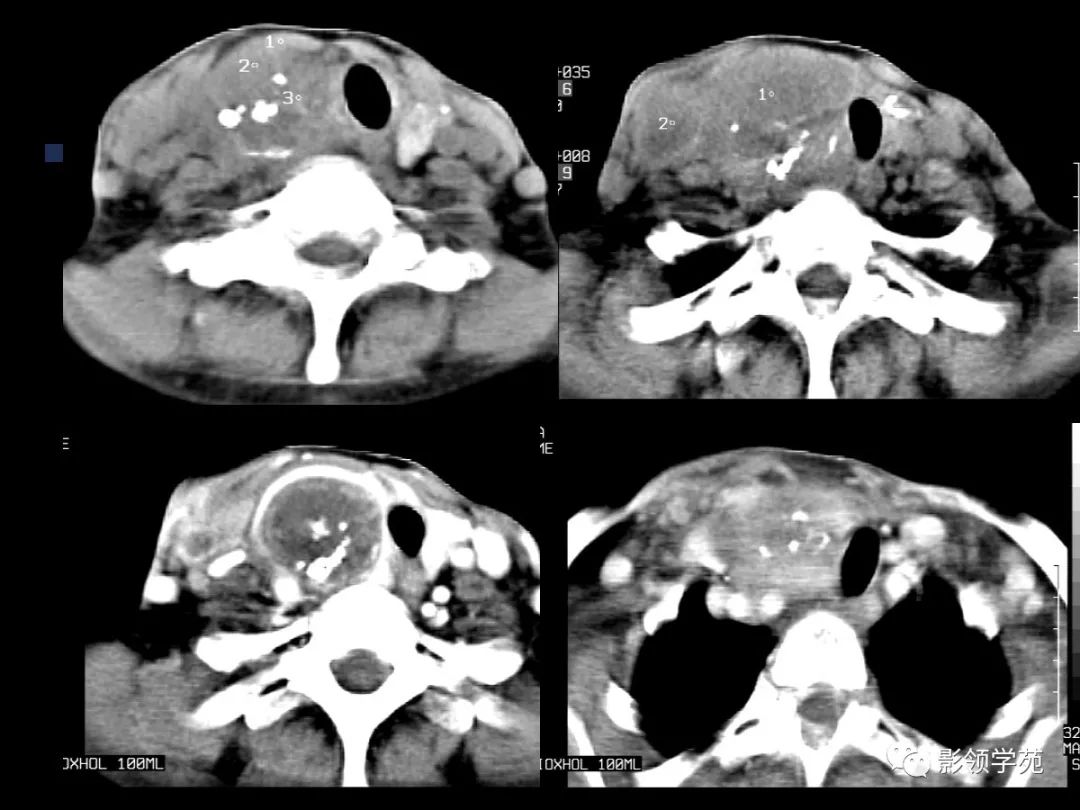

颈部常见疾病影像诊断

- 淋巴结肿大性疾病

- MRI上实性肿块在T1WI上呈等低信号,在T2WI上呈高信号,囊变区呈长T1长T2信号,钙化在T1WI及T2WI上均呈低信号。

- 在增扫时可见环状强化。

- 由于CT和MRI能增强扫描可以清晰显示甲癌的侵润范围和程度,以及显示淋巴结的转移情况